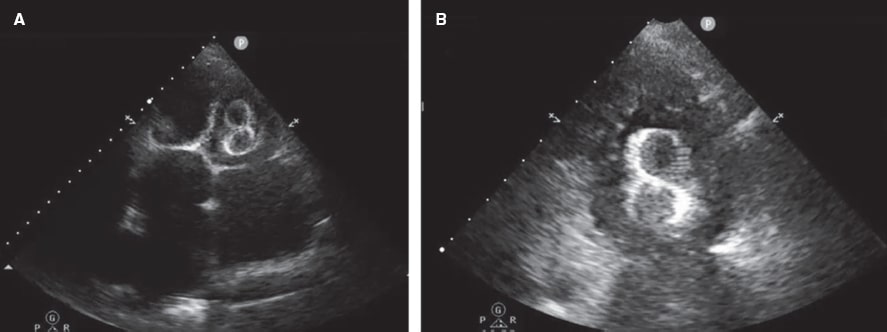

En la figura 5 y la figura 6 se muestran algunos ejemplos de embolización de dispositivos de cierre de la orejuela izquierda.

Figura 6. Ecocardiograma transtorácico (ETT) realizado 24 horas tras el implante de un dispositivo tipo LAmbre de 38 mm. A: se visualiza la migración al ventrículo izquierdo (VI), atrapado por el aparato subvalvular mitral. B: ampliación de la imagen.